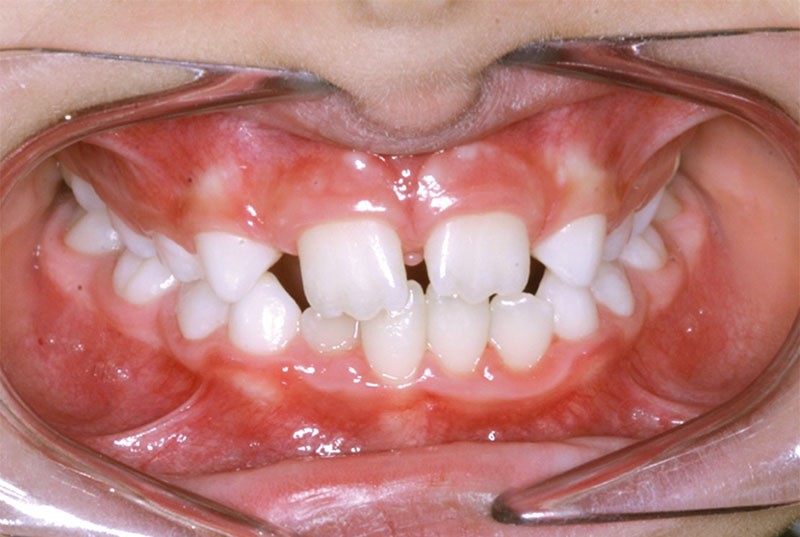

Le traitement orthodontique sans extraction à l’arcade mandibulaire a permis d’établir une occlusion de classe II thérapeutique équilibrée et un sourire harmonieux (fig. 4 et 5).

Une discrète coronoplastie par soustraction a adouci les contours des pointes cuspidiennes canines.